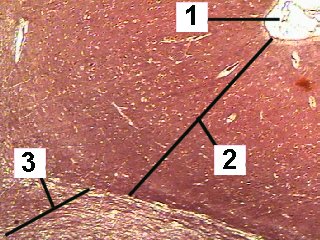

A very low magnification of the cerebrum demonstrating the different layers.

The cortex consists of 6 weakly differentiated layers.